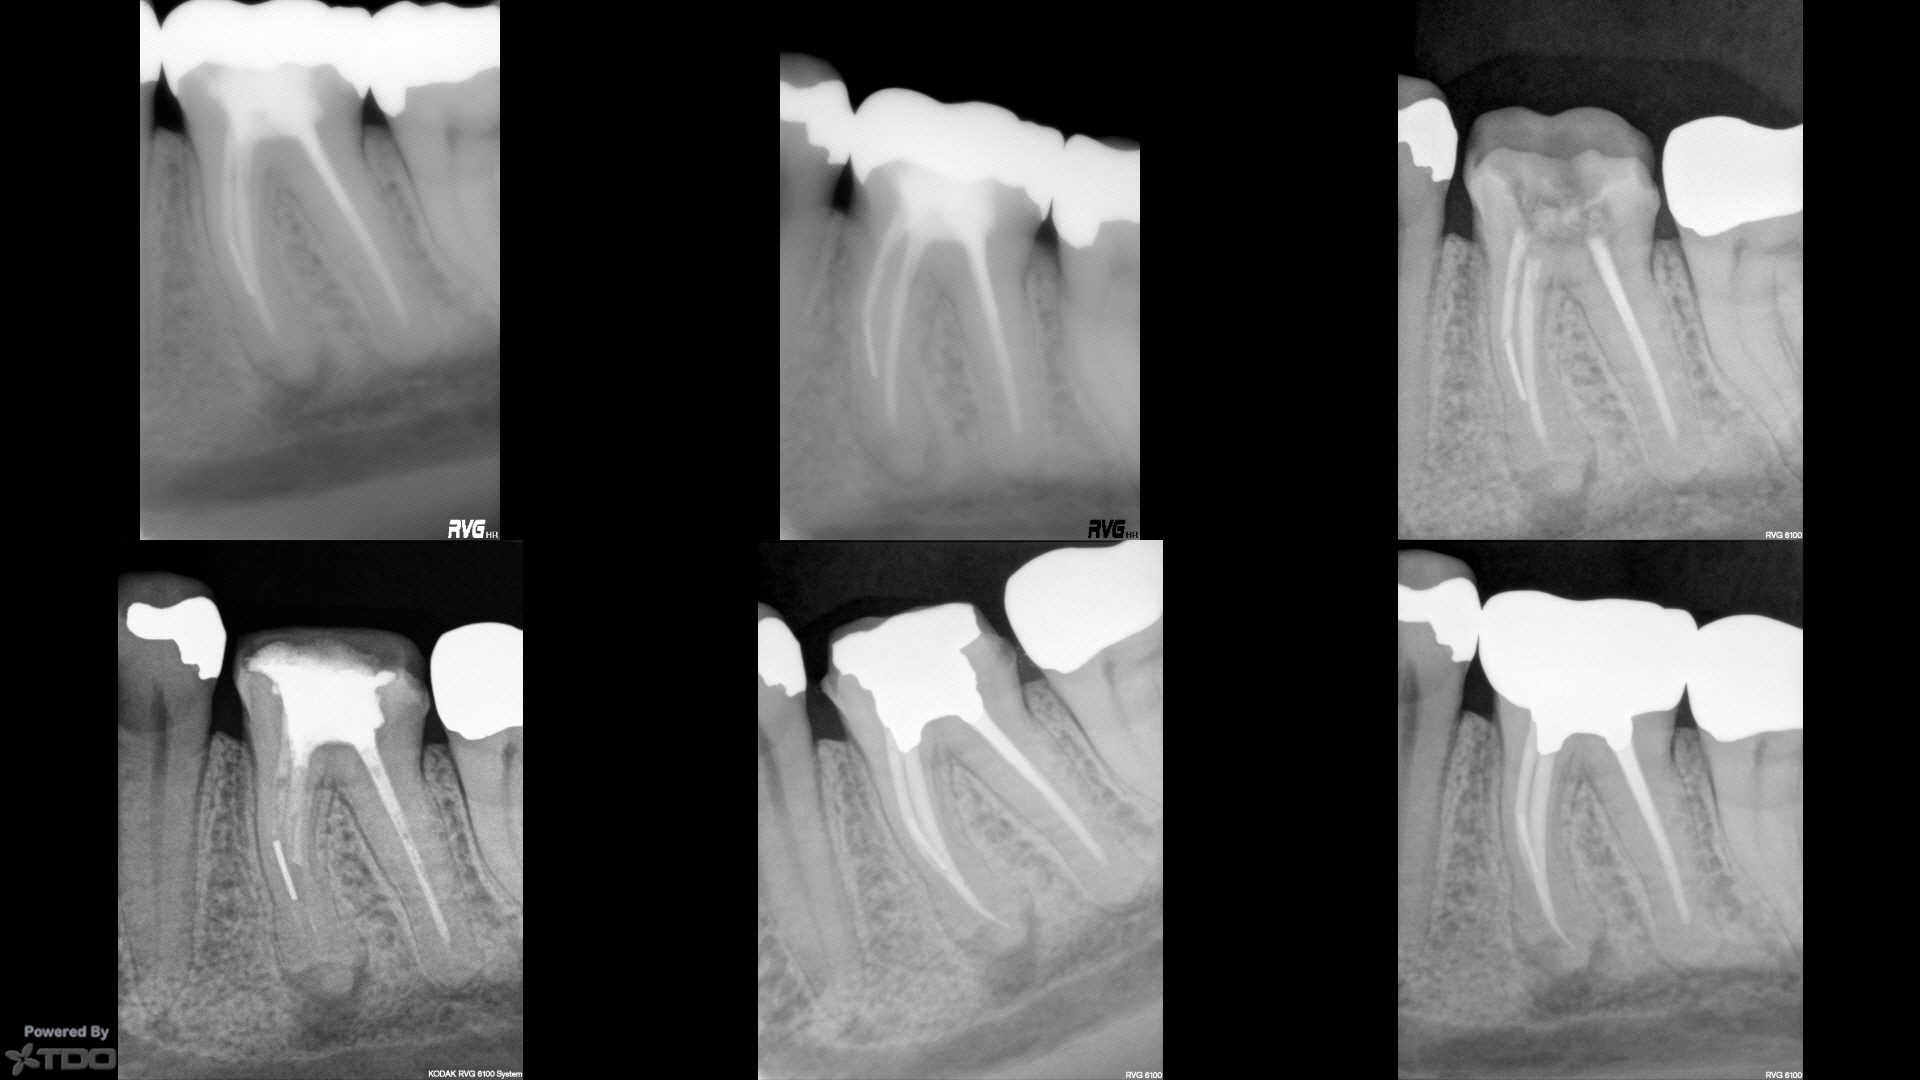

First saw him in 2001 with the separated instrument and finding around the mesial root on this endo that "does not meet the standard of practice in contemporary endodontics."  We thought was about 20 years old at the time.  Only findings were radiographic.  Panel 2 shows a two year followup in my office.  Crown came off in 2013 (panel 3) and was open to the oral environment and full of lunch.  I retreated, but was unable to gain patency and did not really try to get the instrument out.  Completely asymptomatic the whole time.  20/V.06 shapes.

I did the amalgam core, crown preparation and triple-tray impression.  He made the crown and I cemented it with RelyX.  One year followup in panel 6 with the mesial finding seemingly stable.